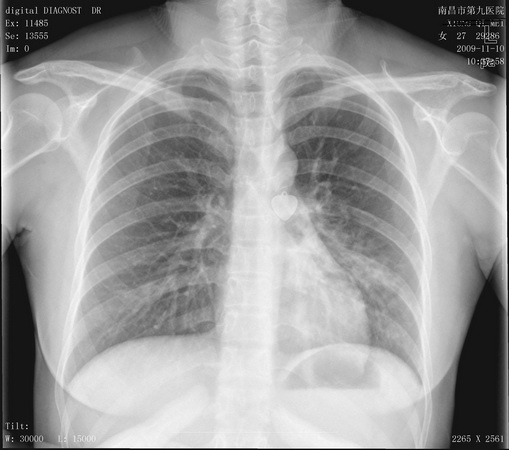

女,咳嗽,咳痰五个月。现低热。

左下肺密度增高模糊,多考虑肺炎,tb不除外,建议ct..

左下肺密度增高模糊,多考虑肺炎,内膜tb不除外,建议痰检,支气管镜检及ct

左肺中下野沿纹理示片絮状模糊阴影,结合临床考虑感染性改变,结核不除外,建议结合实验室检查。

支气管扩张并感染可能性大,肺结核待排,建议进一步检查

痰检找到抗酸杆菌。临床诊断结核。谢谢大家。